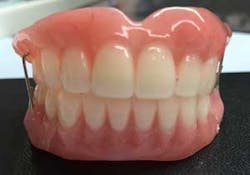

Of course, proper records were obtained in order to fabricate the temporary provisional prosthesis (figure 7), upper and lower, to provide proper function, esthetics, and easy conversion.

Provisional prostheses were then positioned and upon proper stability, function, and cosmetic appearance were torqued to 15 Ncm. At this point, the occlusion was evaluated; posterior occlusion was adjusted to be extremely light, and occlusion associated in the anterior region carried more inter-arch load (figure 11). (2)

The authors strongly believe that with the aggressive nature of her periodontal infection and associated types of bacteria, pathogenic to this aggressive disorder, complete tooth removal and rehabilitation with this protocol will provide this young patient with confidence and enthusiasm about living her life without dental complications (figure 12).